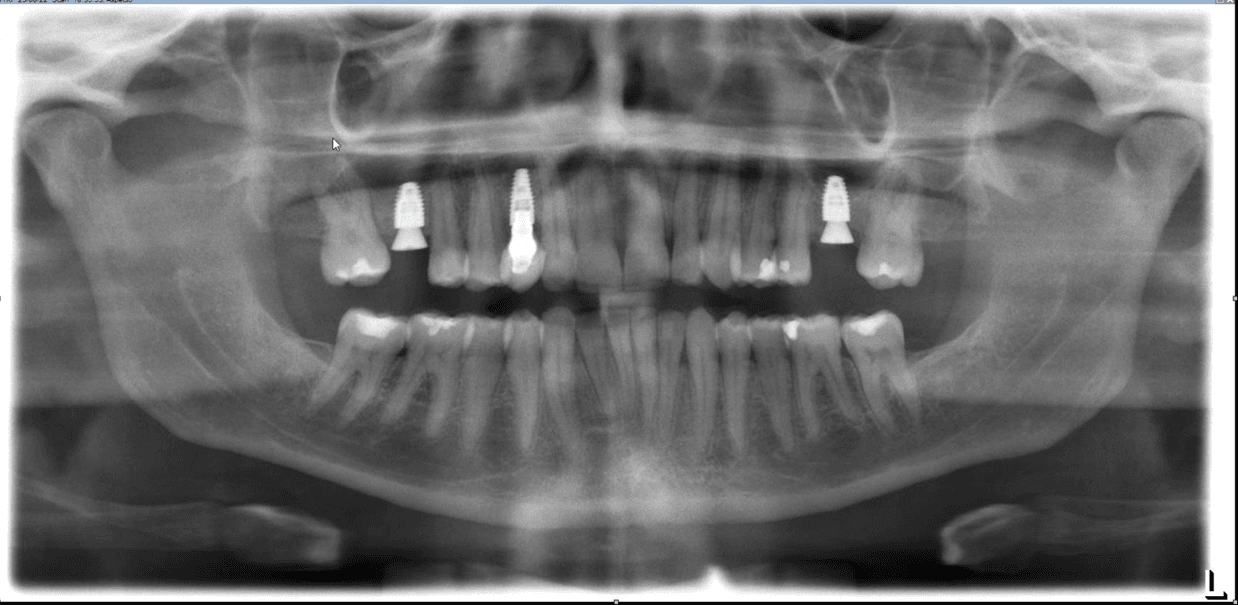

Tracionamento Dentário:

Requer forças mais significativas e direcionadas que os alinhadores sozinhos podem não ser capazes de fornecer sozinhos, com isso, se faz necessário uso de mecânicas auxiliares.

Pode ser feito mas requer um ortodontista experiente para saber direcionar corretamente a movimentação e acessar o dente.

O eixo de saída do dente é muito importante, assim como idade do paciente.

Verticalização de Raízes:

É um movimento que requer muita força, geralmente relacionada a utilização de attachments, elásticos, power arms e mini implantes. Quanto maior a raiz do dente e menos ancoragem o alinhador tiver relacionado aquela área, mais imprevisível o resultado.

Verticalização de molares só tem alguma previsibilidade se for associado a distalização, o que geralmente envolve um planejamento de abrir espaço para implantes e não de tentar fechar esse espaço.

Dentes com inclinação maior que 30º mesmo utilizando mecânicas elásticas não possui previsibilidade.